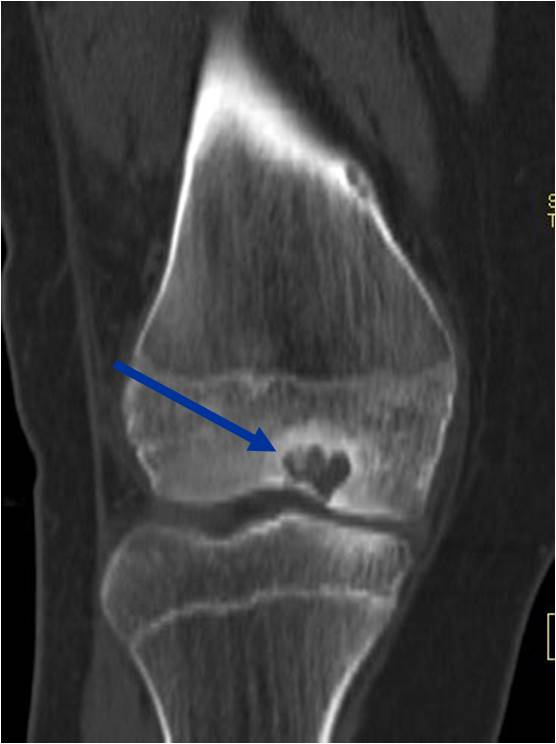

- Presents as a highly defined/well circumscribed geographic oval/round lytic defect

- Surrounded by rim of sclerotic bone

- Usually in epiphyseal region

- May have fine trabeculae and irregular calcifications

- Calcifications are often better detected with a CT scan but are not uniformly present

- Geographic lytic lesion IA/IB margin of sclerosis

- Usually Eccentric more often than Central in the bone

- (CT appearance)

- Most useful for detecting subtle mineralization not apparent on X-rays

- surrounding thin reactive shell of bone/mineralization (Egg Shell Rim of Calcification)

- helps place the tumor in a benign category